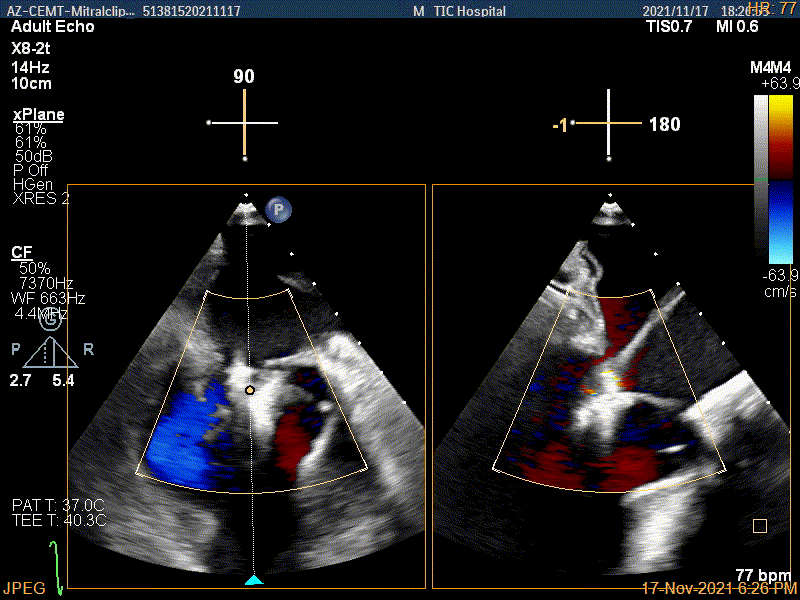

X-plane:下夹子尝试捕获靠近AC区脱垂瓣叶

3D证实夹子内侧残余脱垂(P1区)

3Dcolor证实残余分流主要来源于残余脱垂